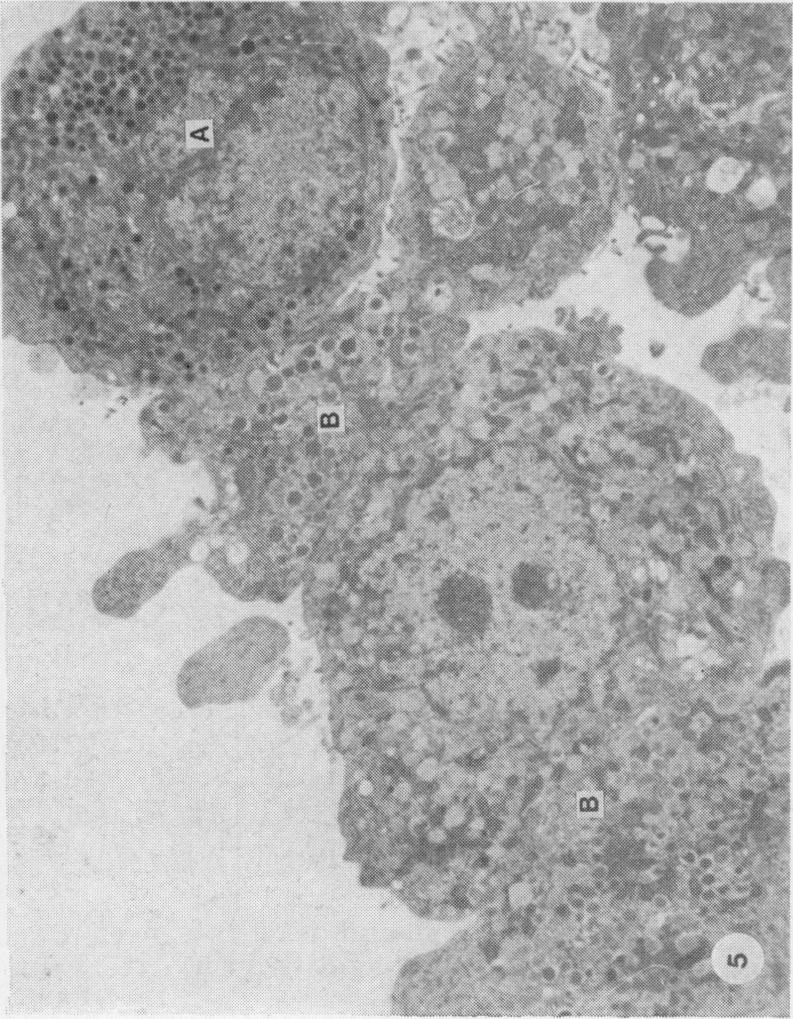

The development of improved methods of islet isolation from the pancreas is hampered by difficulty in identification of islets. A method described by Bensley in 1911 uses neutral red to stain the islets selectively. In the present study the method has been simplified and selective staining of islets in the rat, dog and pig demonstrated by use of light and electron microscopy. Staining of islets with neutral red does not appear to affect their viability as judged by insulin secretion and transplantation in rats.

胰岛从胰腺中分离出来的改良方法的发展受到胰岛识别困难的阻碍。1911年本斯利描述的一种方法使用中性红对胰岛进行选择性染色。在本研究中,该方法已被简化,并通过光学显微镜和电子显微镜证明了在大鼠、狗和猪中胰岛的选择性染色。根据大鼠的胰岛素分泌和移植情况判断,用中性红对胰岛进行染色似乎不会影响其活力。